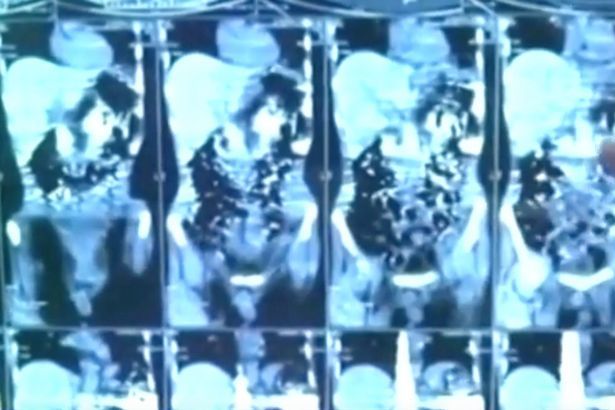

Các ảnh chụp X-quang dạ dày của bệnh nhân khiến các bác sĩ kinh ngạc khi nhìn thấy hơn 40 mảnh kim loại.